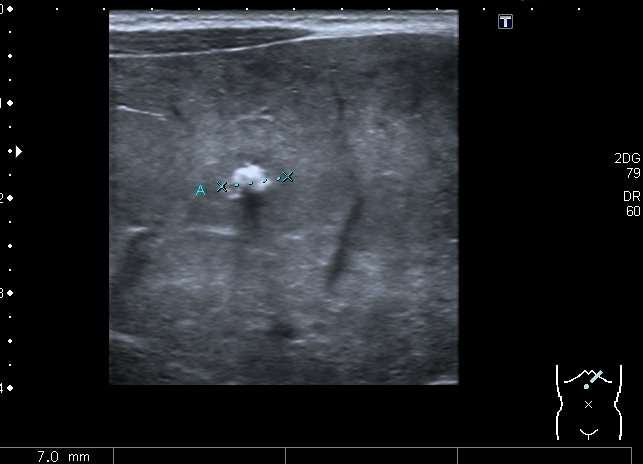

Правый надпочечник представлен округлым гиперэхогенным тканевым образованием с участками кальцификации, гиповаскулярным по отношению к ткани печени и почки